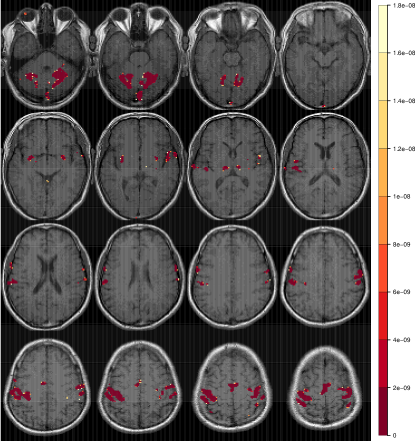

Refer to caption

Figure 2: Radiologic view maps of observed p𝑝p-values of activation of the t𝑡t-test of motor function for (a) the right-hand and (b) left-hand finger-thumb opposition task experiments. For each set of experiments, we display radiologic view maps for the 18th, 19th, 20th and 21st slices (row-wise). The twelve replications are represented column-wise from 1 through 12. For each slice, we display the p𝑝p-values of activation for the thresholded voxels using a t𝑡t-test of the motor function for the twelve replications of the finger-thumb opposition experiment performed by (a) the right hand and (b) the left hand of the same right-hand dominant male volunteer. Note the differences in location and extent of activation over the twelve replications. Note, also the substantial more variability in the experiments performed by the subject’s left hand than on the right.

Figure 2 represents the observed p𝑝p-values of activation for slices 18, 19, 20 and 21 (row-wise) over the twelve replications for both the (a) right-hand and (b) left-hand finger-thumb opposition tasks. (All displayed maps in this paper are in radiologic views and overlaid on top of the corresponding T1fragmentsT1\mbox{T}_{1}-weighted anatomical images.) The specific slices were chosen for display because they encompass the ipsi- and contra-lateral pre-motor cortices (pre-M1), the primary motor cortex (M1), the pre-supplementary motor cortex (pre-SMA), and the supplementary motor cortex (SMA). Clearly, there is some variability in the results for the right-hand task. In Figure 2a for instance, all experiments identify activation in the left M1 and in the ipsi-lateral pre-M1 areas, but there is some modest variability in the identified activation in the contra-lateral pre-M1, pre-SMA and SMA voxels, with some experiments reporting very localized or no activation and others having these regions as activated and somewhat diffused in extent. Slices for the left-hand finger-thumb opposition task experiments in Figure 2b, on the other hand, show far more variability, both in location and extent. It is interesting to note that while most experiments identify activation in the right M1, the ipsi-lateral, contra-lateral pre-M1, pre-SMA and SMA areas, they also often show activation in the corresponding left regions. The case of the eighth replication is extremely peculiar. Most of the activity in the four slices are in the left areas and the right areas have little to no activation. This makes one wonder if the naturally right-hand dominant male volunteer had, perhaps unintentionally and out of habit, used his right hand instead of his left in performing some part of the experimental paradigm. In summary, there is clearly far more variability in the left hand set of experiments than in the right hand set. We now assess the reliability in each set separately.